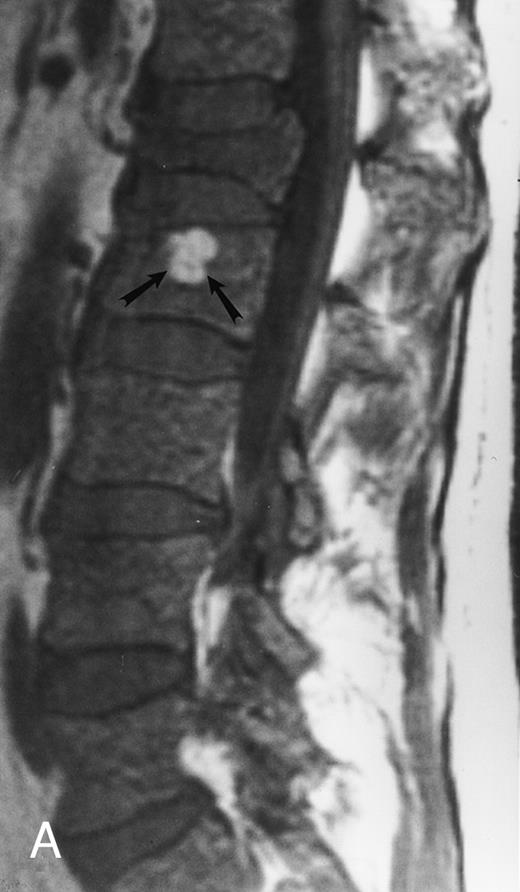

Focal MR pattern of abnormal marrow in a 48-year-old man with multiple myeloma: T1-weighted (500/10, TR/TE) (A), T2-weighted, fat-suppressed fast spin echo (5000/96, TR/TE, ET 16) (B), and enhanced T1-weighted (500/10, TR/TE) (C) sagittal MR images of the lumbar spine. Focal lesions (arrows) in L2 and S1 are dark in (A), bright in (B), and in (C) they enhance and become almost imperceptible from the uninvolved marrow.